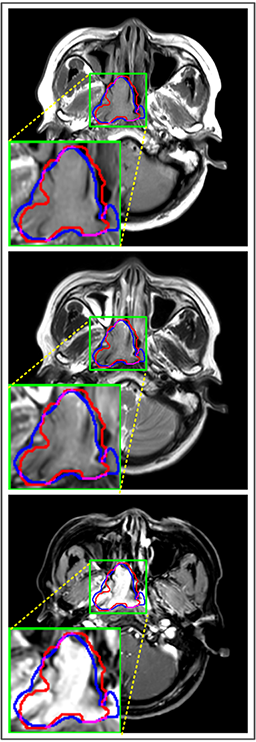

Comparison with ground truth. Some predicted results of MMFNet are shown in 2D images and 3D images in Figure 7 and Figure 8. As shown in these figures, although the shape and size of NPC are varied from each other, MMFNet can still accurately determine the regions of NPC and obtain the accurate contours of tumors. Through analyzing 2D images in figure 7, MMFNet has a capacity to fuse multi-modality MRI to reduce the confusion brought by intensity’ similarity between nearby tissues and NPC. The values of , and of MMFNet are shown in Table 1. MMFNet can reach the best results with , and .

Comparison with related works. Table 1 reports the values of , and for different methods. Predicted masks of different methods are illustrated in Figure 9 and Figure 10, which respectively present results in 2D and 3D images. Through comprehensively analyzing these results, the proposed MMFNet actually have the following properties:

(i) It directly fuses 3D MRI images rather than 2D slices. Thus, it can effectively use meaningful information from neighboring slices of MRI to realize NPC segmentation. As shown in Table 2, MMFNet can bring , and improvements in and compared to the best method based on 2D images (Multi-modality patch-based CNN). And Figure 10 shows that 3D-based methods have less isolated regions (false positives) than 2D-based ones.

(ii) It segments NPC by fusing multi-modality MRIs with the multi-encoder network. Thus, it can learn complementary and interdependent features from different modalities of MRI for final decisions. Additionally, comparing with input-level fusion networks and decision-level fusion networks, layer-level fusion networks (including MMFNet) can effectively capture informative features from different modalities of MRI and fuse low-level features and high-level features.

(iii) It uses a fusion block to fuse low-level features from different modalities of MRI and prepare these low-level features for the fusion with high-level features. Thus, it can more effectively fuse information from various sources. It also uses the self-transfer strategy to initialize the netwerk. Hereby, it can stimulate encoders to make full mining of meaningful features from modality-specific MRI. And it finally improve base multi-encoder-based network (Merging encoders’ fetures) by , and in and .